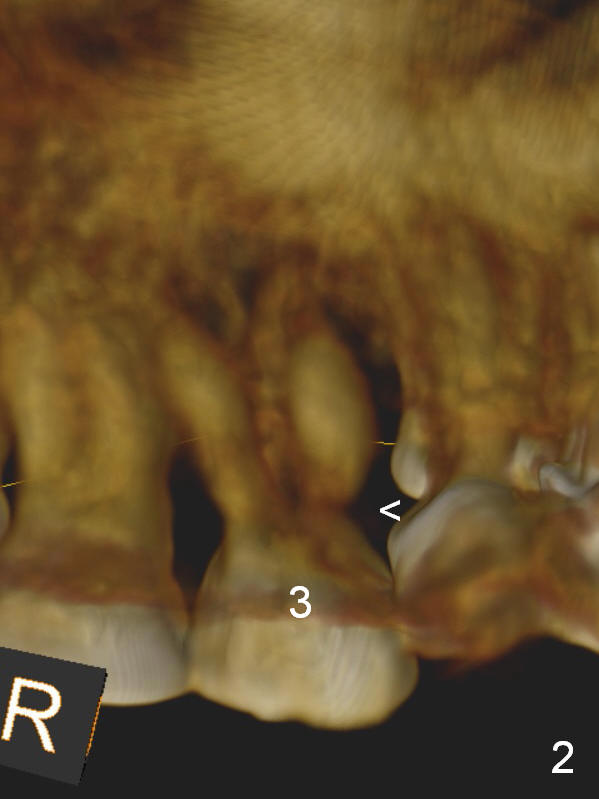

In addition to supraeruption of the teeth #2 and 3, the caries in the mesiobuccal root of #3 seems to be beyond salvation (Fig.1,2 arrowhead). When the implant at #3 is osteointegrated, a provisional restoration is placed (Fig.4 pink). Brackets (white boxes) are placed at differential levels among #1-3 to initiate regional orthodontic treatment using #3 as an anchorage. Mini-implants are placed if necessary. The tooth #1 is extracted after the limited ortho. Scaling & root planing will be done first.